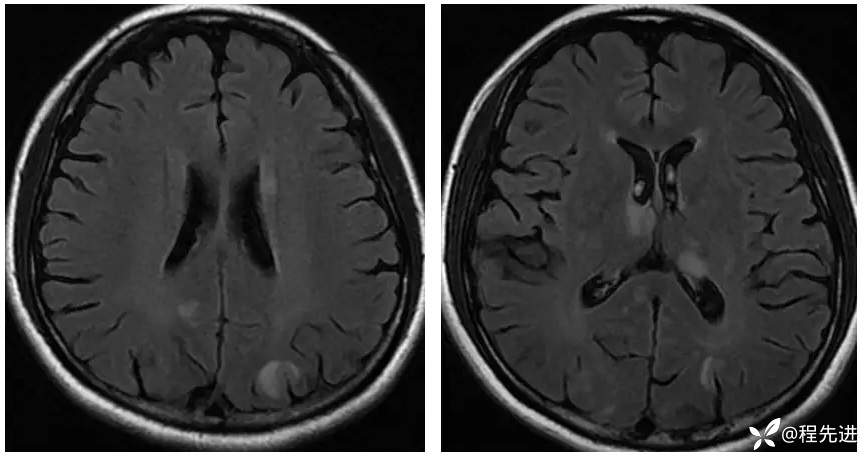

【现病史及既往史】:孕期38周,蛋白尿10天,血压升高6天,剖腹产后一天出现头晕,头痛,嗜睡。既往糖尿病史

查体:不配合,血压波动,130-157/85-109mmHg

影像检查: